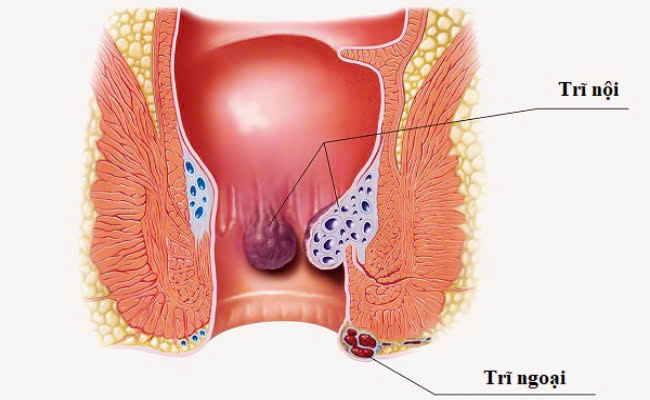

Táo bón không chỉ gây khó khăn trong việc đi ngoài mà còn là nguyên nhân hàng dẫn đến bệnh trĩ nếu không được điều trị kịp thời. Khi bị táo bón, người bệnh phải dùng sức để rặn mới có thể đẩy phân ra ngoài. Việc rặn quá mức này làm tăng áp lực lên các vùng tĩnh mạch ở hậu môn và trực tràng, làm chúng bị giãn ra bất thường. Đến một mức độ nào đó, các tĩnh mạch này sẽ bị sưng lên và hình thành các búi trĩ.

Búi trĩ hình thành như thế nào?

- Vị trí: Búi trĩ có thể xuất hiện ở bất cứ đâu, bên trong hoặc bên ngoài hậu môn hoặc nằm sâu trong trực tràng.

- Triệu chứng: Người bệnh thường cảm thấy đau, ngứa ngáy, chảy máu mỗi khi đi vệ sinh. Hậu môn và trực tràng là khu vực có độ ẩm cao, dễ bị nhiễm khuẩn nhiễm trùng nếu không được bảo vệ đúng cách. Búi trĩ có thể bị nhiễm trùng hoặc hình thành cục máu đông, làm tăng mức độ đau và gây mất máu .